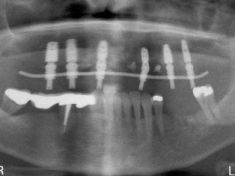

Paziente con problemi parodontali. Sono stati estratti i denti residui in arcata, inseriti gli impianti e, dopo poche ore, inserita la protesi

Paziente con problemi parodontali. Implantologia a carico immediato

Implantologia post estrattiva a carico immediato